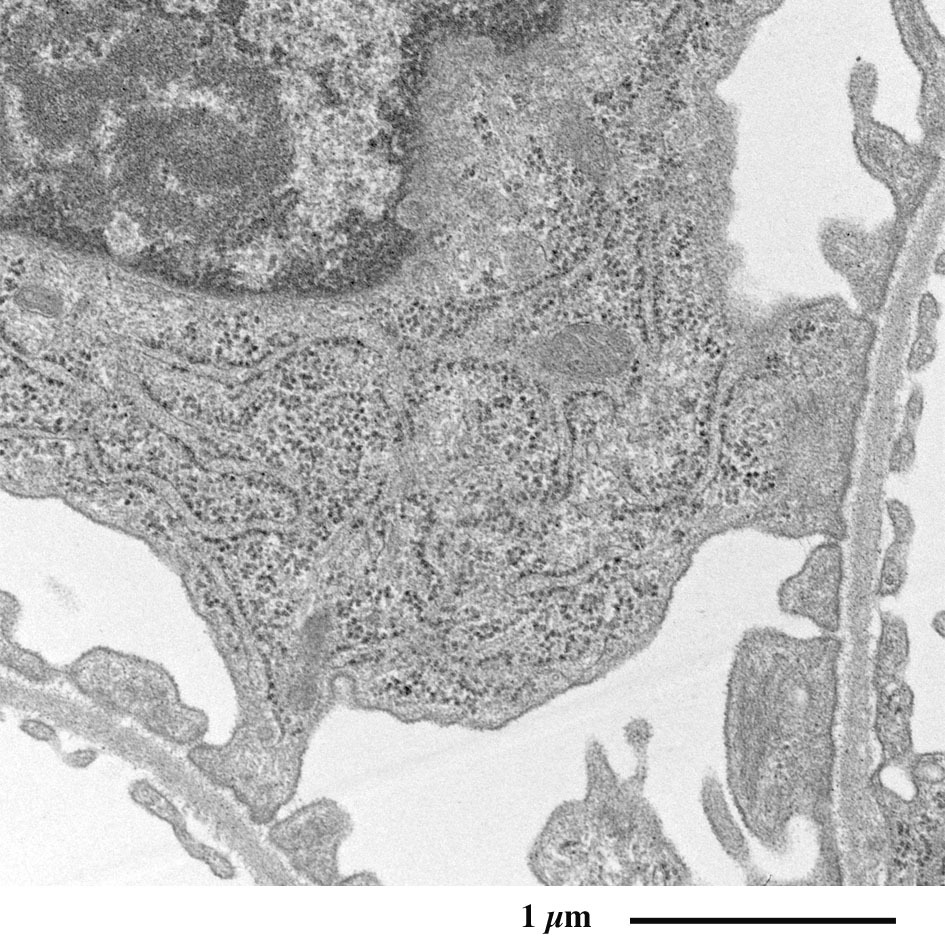

糸球体の電子顕微鏡像

足細胞を含むボウマン腔を縫うように毛細血管が走行し、

外周をボウマン囊が取り囲みます。

糸球体の拡大像

足細胞の突起が毛細血管の外周を取り囲む様子が観察されます。